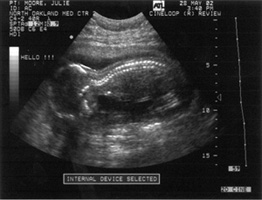

10/04/02 07/18/78

19 weeks 37 1/2 weeks